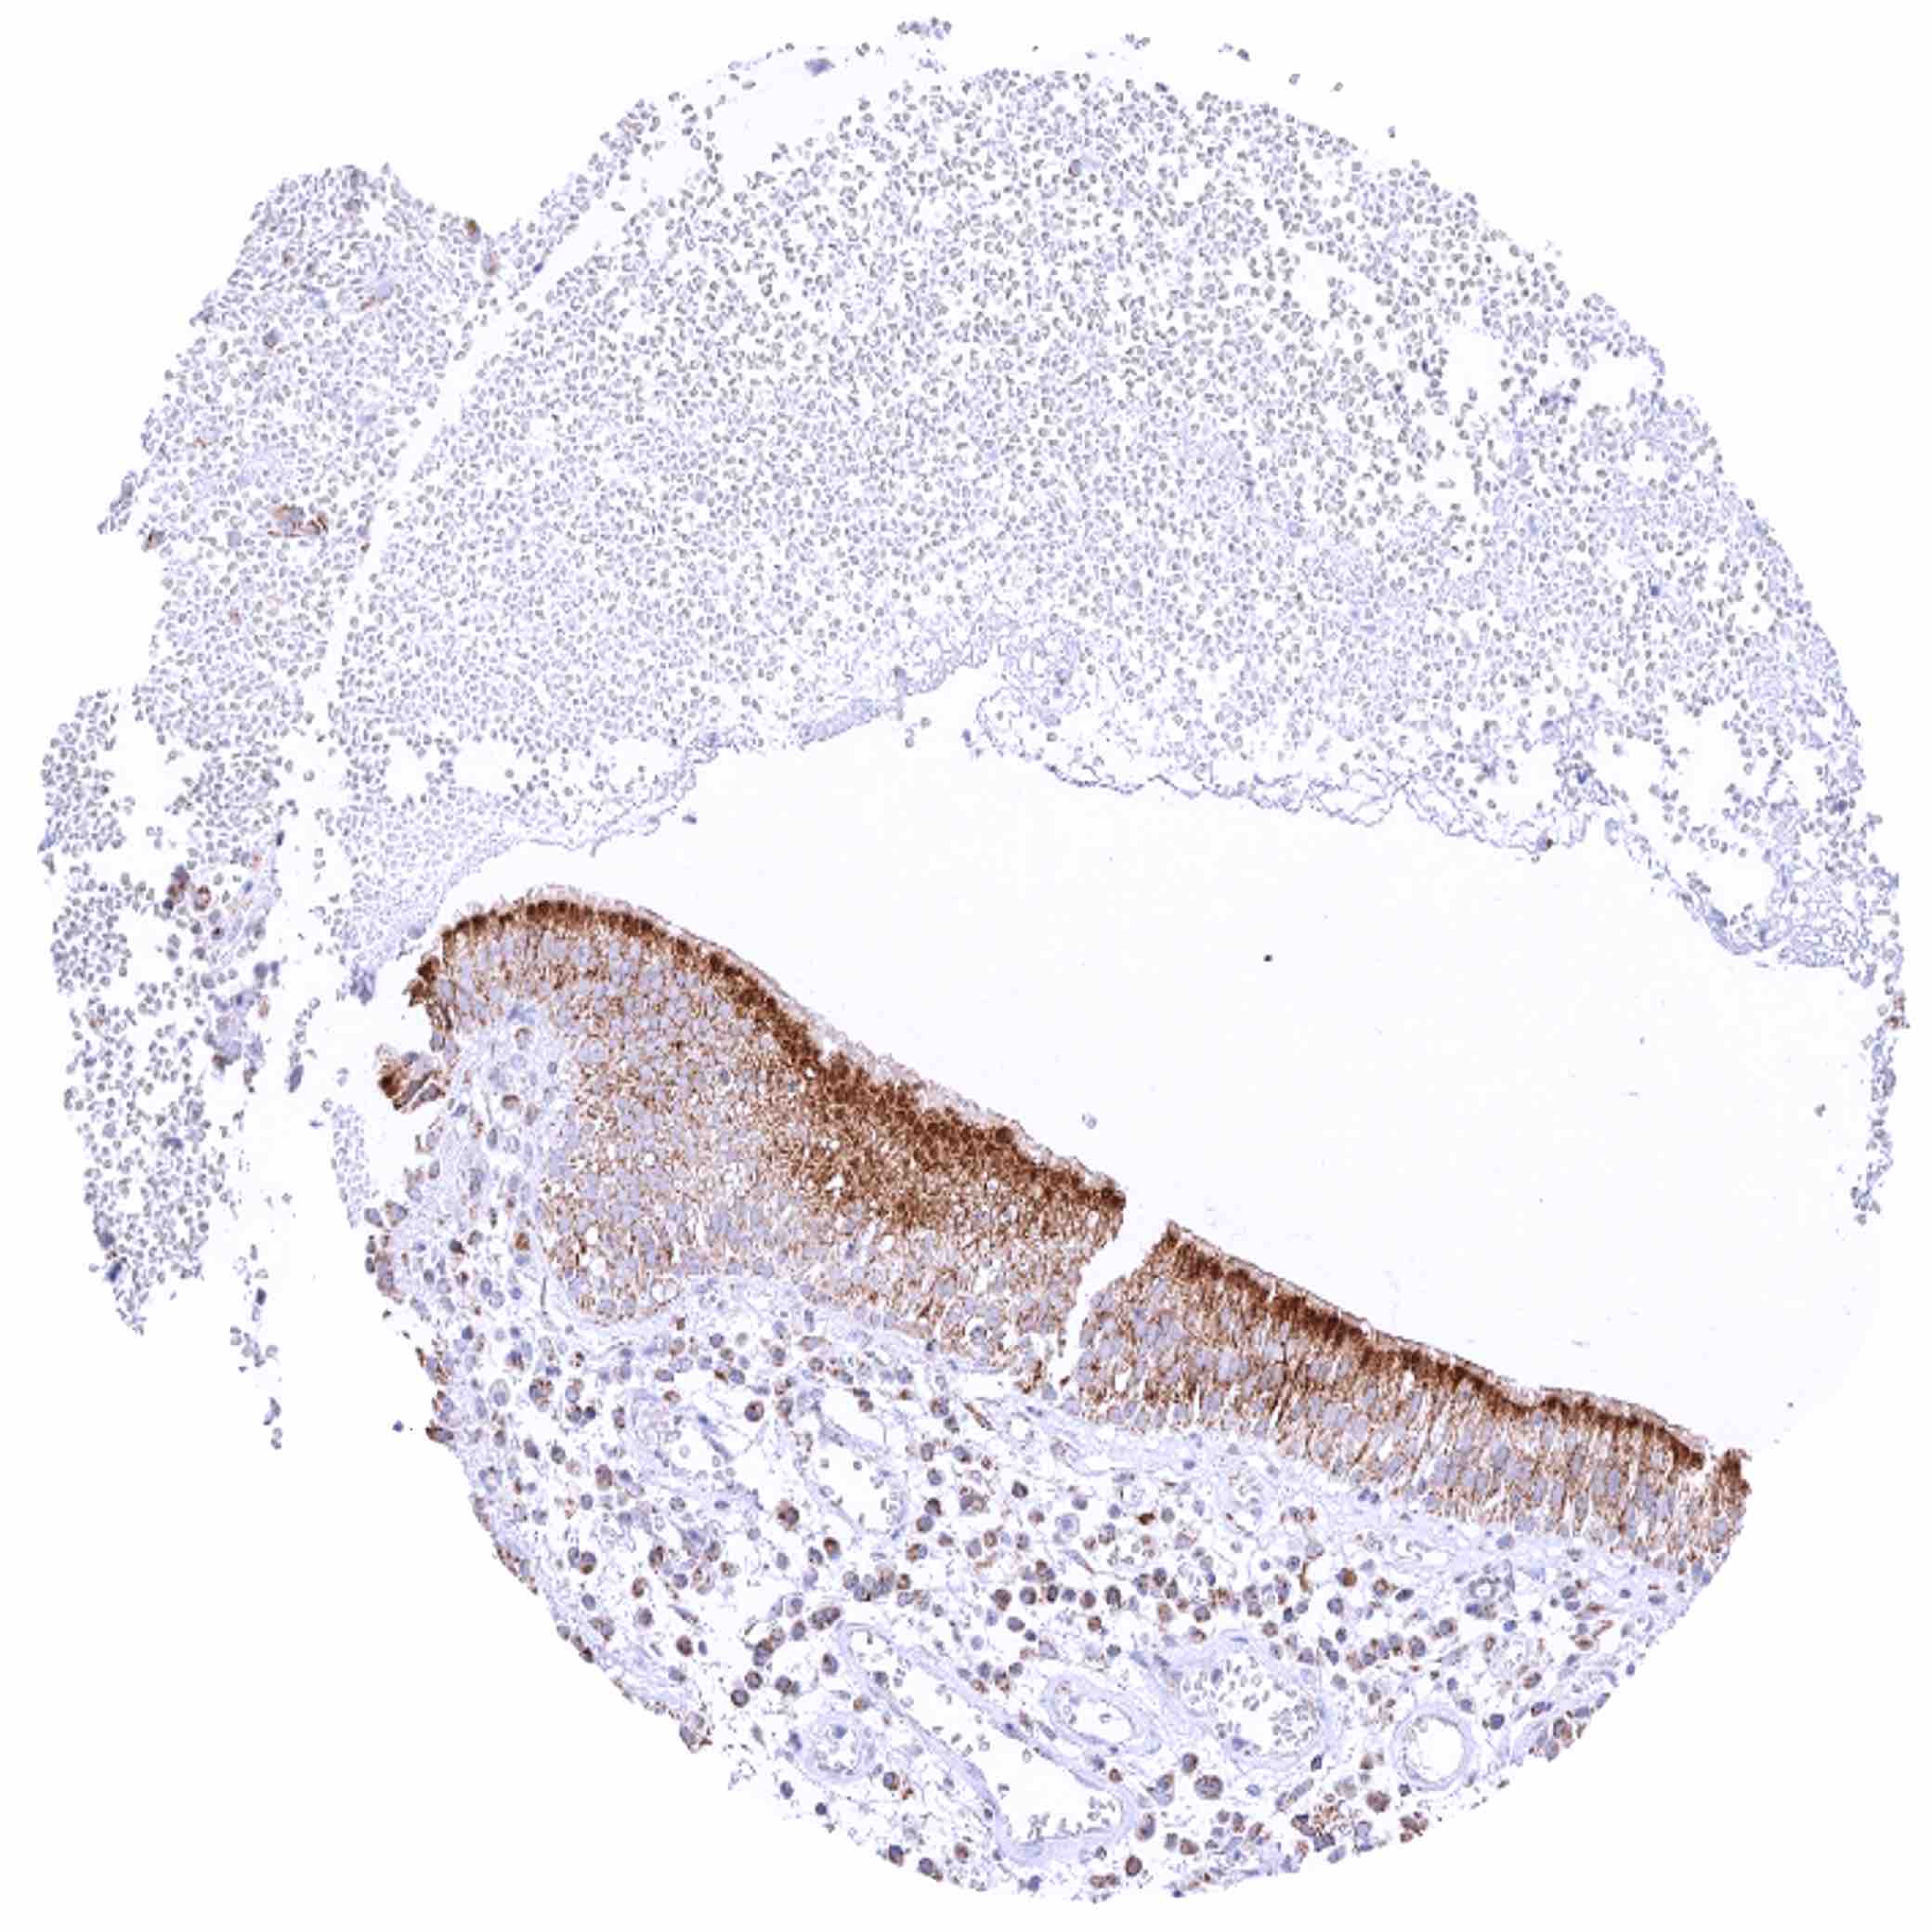

Bronchus, mucosa – Marked granular cytoplasmic SDHB staining of epithelial cells, predominately in the sub-apical compartment